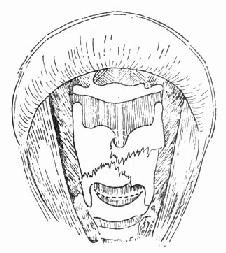

1.症状 急性声门下喉损伤为环状软骨骨折(图96-15),或有或无贯穿喉损伤。如果发现有环状软骨与气管间断裂也可按声门下损伤处理。

图96-16 喉正中裂口术

图96-17 内置扩张模示意图

4.手术方法 ①低位颈部横切口,皮瓣包括颈阔肌。②低位气管切开术,切开第6~7气管环,置入气管套管。③喉正中裂开术,同时切开气管环1~3环(图96-16)。④修复喉粘膜裂伤。⑤置入硅橡胶或牙模脑扩张模,扩张模上界平室带水平,下界在第2气管环水平,经皮肤甲状软骨穿过金属线固定扩张模,皮肤处将金属线固定在钮挰上,钮扣用酒精棉球覆盖(图96-17)。⑥尽量使骨折的环状软骨、甲状软骨复位并缝合软骨膜。缝合第1~3气管环。⑦逐层缝合软骨膜,皮下组织,皮肤,关闭切口,无菌包扎。⑧术后6~12周于直接喉镜下去除喉扩张模。⑨取出扩张模后试行堵管,无呼吸困难即可拔管。